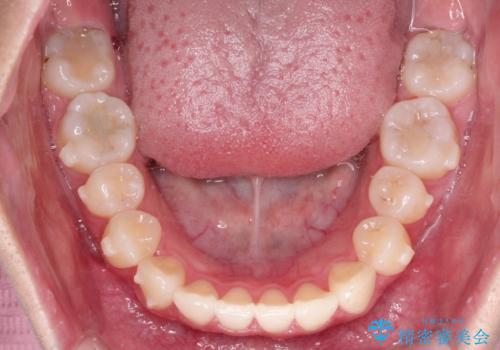

前歯のがたがたを綺麗にしたい

- 前歯がねじれていること、出ていることを主訴に来院されました。

前歯の突出感も改善され、満足していただきました。